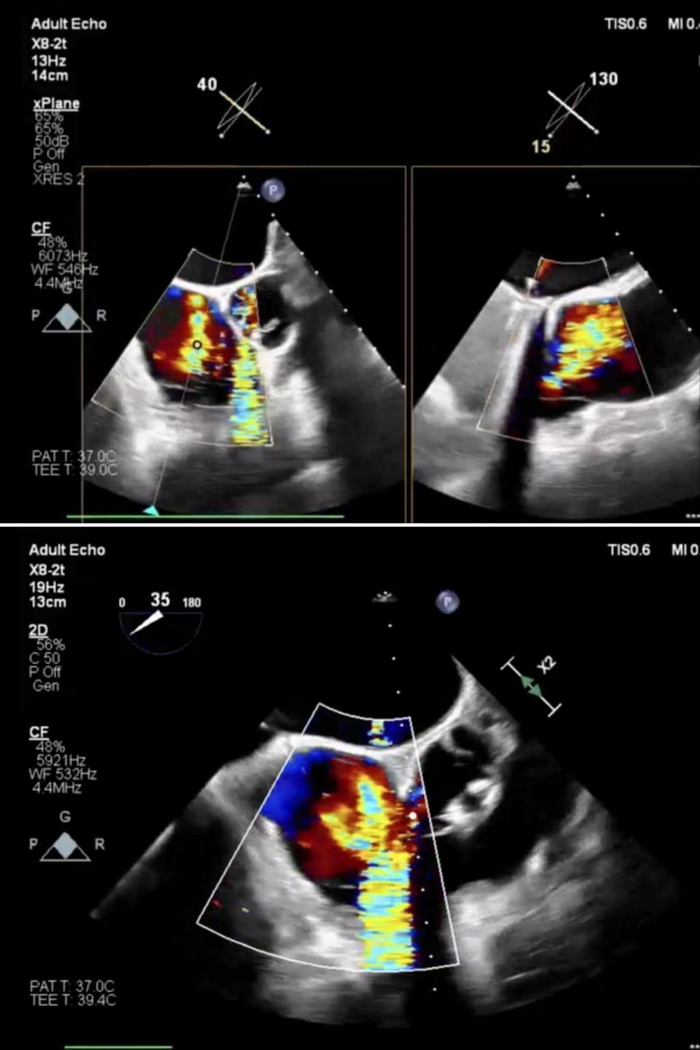

患者老年女性,因“双下肢水肿,伴活动后四肢乏力半年”入院。既往二尖瓣置换术20多年,高血压病史20年、糖尿病史4年。心脏超声检查示:三尖瓣重度反流。入院诊断有心脏瓣膜病、三尖瓣关闭不全(重度)、主动脉瓣关闭不全(中度)、肺动脉高压(中度)、二尖瓣置换术后 心功能IV级(NYHA分级)、高血压(2级,很高危)、2型糖尿病 、心律失常、持续性房颤。 STS评分示外科手术高危。经食道超声提示:右心房扩大,瓣环扩张,瓣叶拴系高度6mm,隔叶栓系引起前叶、后叶与隔叶间错位,后隔间隙最宽约8.8mm,反流缩流颈宽度12.7mm,反流量68ml,右房面积21.7cm2,TAPSE:23mm。

患者全麻后,行右侧颈静脉穿刺,将12T K-Clip®系统送达右心房内。在经食道超声引导下,对K-Clip®系统进行调姿,指向目标瓣环区,将K-Clip®锚定到位,打开夹持臂到最大角度,夹合,评估反流改善情况,解离器械退出系统。同样方法将14T K-Clip®系统夹合于前后瓣交界处。超声评估示反流下降至轻—中度,冠脉造影示冠脉血流与术前相同,达到满意效果,缝合血管,手术结束。患者术前重度三尖瓣反流。术前三尖瓣环面积10.3cm²,周长11.5cm;术后三尖瓣环面积6.6cm²,周长9.3cm。